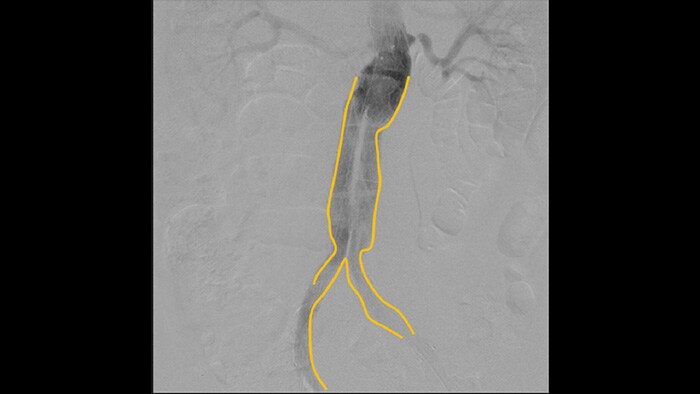

With the Philips Zenition mobile C-arm, Dr. Vila is obtaining outstanding high-quality images that allow him to perform most vascular procedures at the low dose setting.

With the Zenition, our DSA image quality has improved greatly. We no longer see a grainy image. We just see a very clear image."

Dr. R. Vila, MD

Digital subtraction angiography (DSA) is used in interventional vascular procedures to clearly visualise blood vessels by removing structures that can obscure vessel visibility. Roadmap fluoroscopy overlays a previously acquired subtracted contrast image on the live fluoroscopy, allowing you to track a device without reinjecting contrast.

Use the Outlining tool to easily mark a bifurcation or side branches by simply drawing on the monitor of the Mobile Viewing Station with your finger or an externally connected mouse.